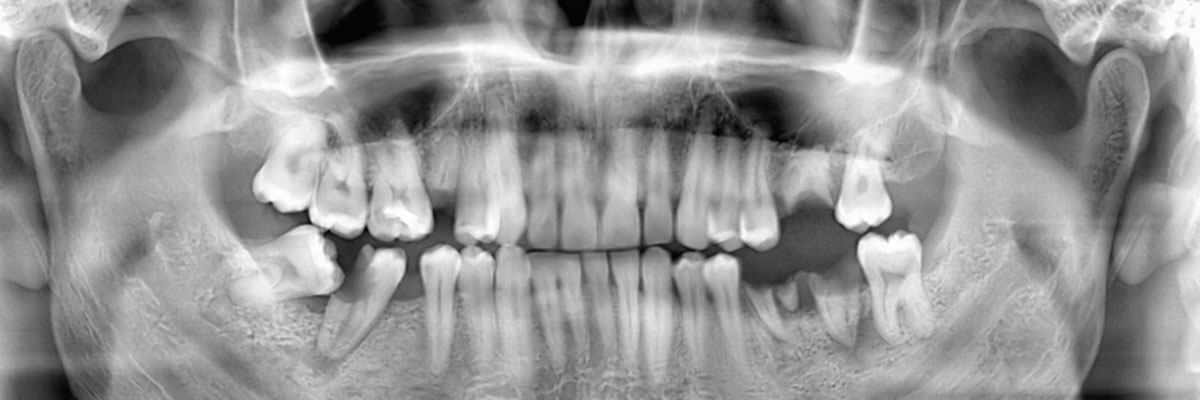

We recommend that you call 281-693-3330 and schedule an appointment with our dental office as soon as your tooth has either fallen or been knocked out. During your appointment, we will examine your gums, take X-rays, and make a recommendation as to which tooth replacement option will be best suited for your needs. Acting on this quickly will help in restoring your appearance and oral health.